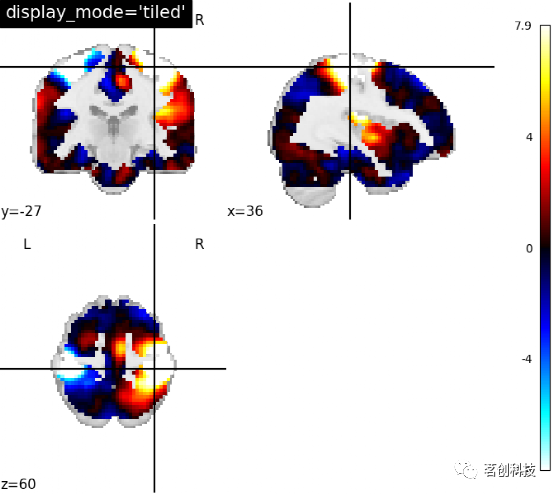

设置display_mode= 'tiled',cut_coords=[36, -27, 60],Tiled slicer表示沿着x, y, z方向进行3次切割,以2×2的网格进行排列。

plotting.plot_stat_map(stat_img, display_mode='tiled',

cut_coords=[36, -27, 60],

title="display_mode='tiled'")